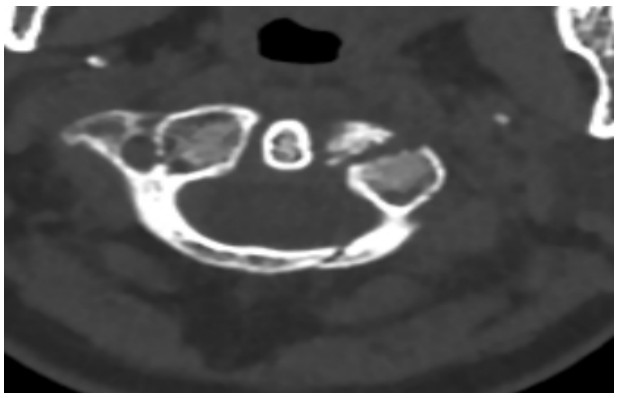

國慶節(jié)前一天,譚女士不幸被門框砸傷頸部,劇烈的疼痛和頸椎的活動受限讓她的世界瞬間陷入了黑暗。在經(jīng)歷了初步的檢查后,譚女士被診斷為寰椎骨折,這個診斷如同一道晴天霹靂,讓她和家人的心沉入了谷底。絕望中,譚女士被緊急轉(zhuǎn)至衡陽市中心醫(yī)院骨科一區(qū)(脊柱外科),錢軍博士及其團(tuán)隊(duì)在接到這一緊急病例后迅速接診,經(jīng)過細(xì)致的病史詢問、體格檢查和影像學(xué)資料分析,確診譚女士的寰椎骨折伴有寰樞椎體不穩(wěn)定,迫切需要手術(shù)治療以恢復(fù)其穩(wěn)定性。考慮到上頸椎手術(shù)的高風(fēng)險性,特別是寰樞椎周圍結(jié)構(gòu)復(fù)雜,緊鄰椎動脈和脊髓,手術(shù)過程中的任何微小失誤都可能導(dǎo)致災(zāi)難性后果,錢軍博士團(tuán)隊(duì)頂著壓力,迎難而上,沒有絲毫猶豫,立即行急診手術(shù),投入到緊張的救治工作中。